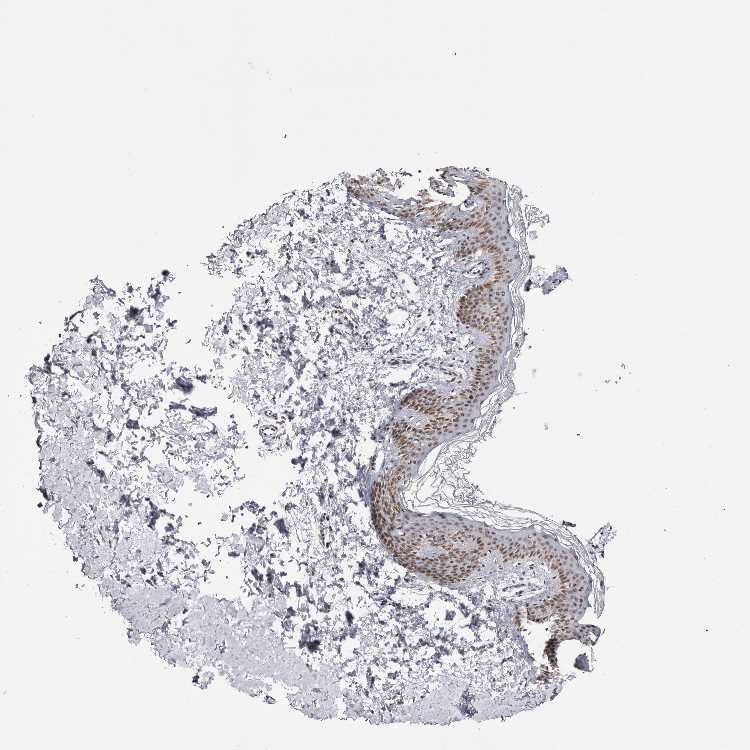

SKIN 1 - Antibody stainingi

Antibody staining in the annotated cell types in the current human tissue is reported as not detected, low, medium, or high, based on conventional immunohistochemistry profiling in selected tissues. This score is based on the combination of the staining intensity and fraction of stained cells.

Each image is clickable and will lead to virtual microscopy that enables deeper exploration of all samples and also displays staining intensity scores, fraction scores and subcellular localization as well as patient and tissue information for each sample.

Antibody CAB025404

Cells in basal layer Medium

Cells in corneal layer Not detected

Cells in granular layer Medium

Cells in spinous layer Medium

Endothelial cells Medium

Extracellular matrix Not detected

Fibrohistiocytic cells Medium

Langerhans cells Medium

Lymphocytes Medium

Melanocytes Low

Vascular mural cells Not detected